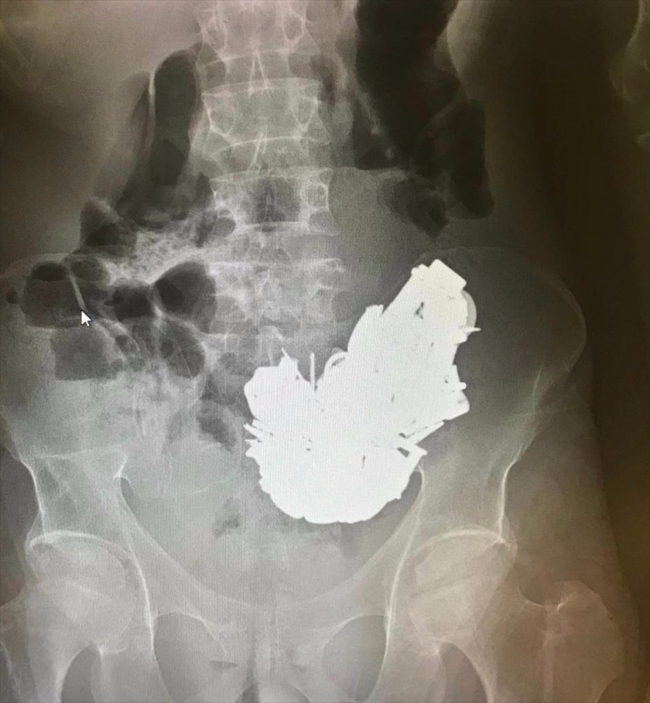

Midesinden 200'e yakın metal cisim çıkarılan hasta kurtarılamadı

İzmir'de karın ağrısı şikayetiyle hastaneye götürülen ve midesinden 580 gram ağırlığında yaklaşık 200 cisim çıkarılan hasta kurtarılamadı.

Doktorlar, röntgen filminde midede çok sayıda cisim bulunduğunu tespit etti. Sağlık durumu kötüleşen hasta için acil ameliyat kararı verildi.

Hastanın midesindeki farklı boyutlarda ve toplam 580 gram ağırlığında yaklaşık 200 cisim, 3 saat süren ameliyatla alındı.

Hastanın midesinden çıkarılan cisimler arasında bulunan mıknatıs, anahtar, boş kovan, çivi, cıvata, anahtarlık, madeni para, metal harfler ve çeşitli boyuttaki metaller, sağlık personelini şaşırttı.

Midedeki metallerin mıknatıs sayesinde bir arada toplanması, röntgen görüntüsüne de yansıdı.

Operasyonun ardından yoğun bakım servisine alınan hasta, zehirlenmeye bağlı olarak hayatını kaybetti.

Cerrahların hastayı kurtarmak için zamanla yarıştığını ancak hastaneye çok geç başvuran hastayı kurtarmakta başarılı olamadıklarını aktaran Göksel, "Midedeki metallerin çıkarılmasına rağmen metal ve mıknatısa bağlı zehirlenme nedeniyle hasta kurtarılamadı" dedi.